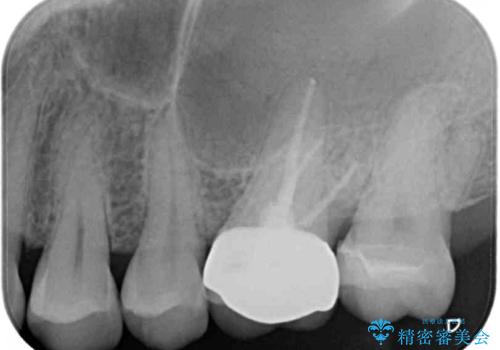

強い咬合力を負担する第一大臼歯であるため、根管治療後は速やかにオールセラミッククラウンにて補綴治療を行うこととしました。

神経組織は壊死が始まっておりましたが、初回処置後には痛みを感じることもなくなり、2回目に無事に根管治療を終えることができました。